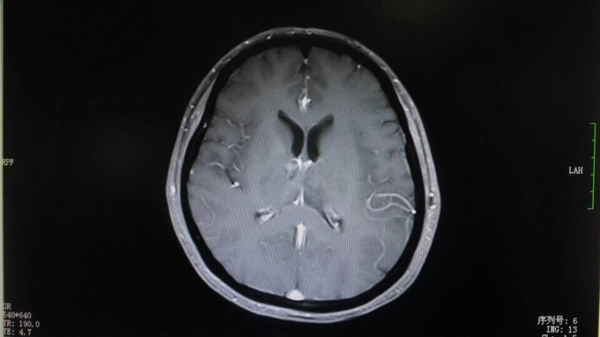

治疗后刘女士的肿瘤缩小到5mm×3mm